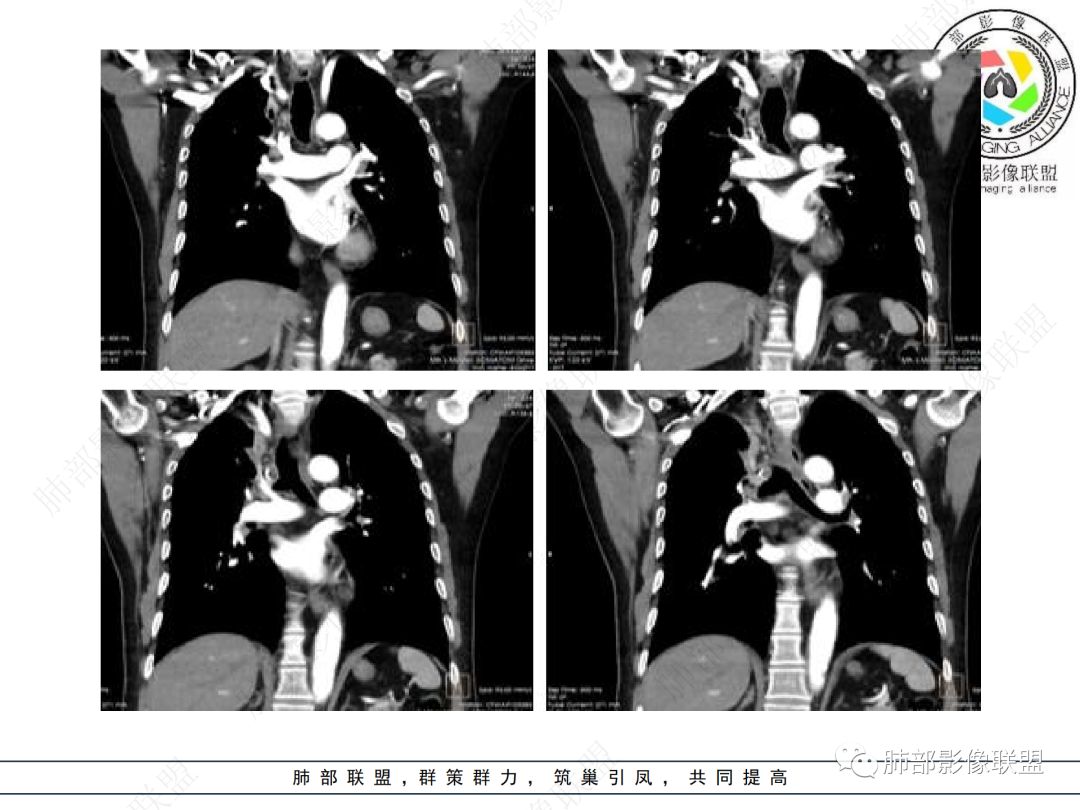

主要在慢性炎性病变与腺癌之间鉴别,病灶有膨胀性生长,支气管未见阻塞,支气管僵硬,增强病灶内可见强化,支气管内部壁增厚,偏向占位性病变,腺癌可能。

右肺上叶可见一团块影,边界清,有膨隆有凹陷,边缘可见毛刺,斜裂可见牵拉,不均匀强化,内可见液化,临近支气管未见明确阻塞,考虑腺癌可能,鉴别脓肿,结核等

病史2年。右肺上叶团片影,边缘部分清晰,平直,相邻纵隔侧胸膜黏连较广泛,周围见斑点。增强均匀强化。首选炎性肉芽肿性病变(慢性炎症,结核)。肿瘤性病变待排。食道上段形态异常建议相关检查。

右肺上叶团块,边缘毛糙,长索条,周围斑点影,邻近胸膜增厚,不均匀强化,其内小低密度灶边界清,考虑炎性肉芽肿,腺癌待排

老年男性,咳嗽2年,右上肺类圆形新生物,毛刺,不均匀强化,考虑肺癌,支气管截断不明显,腺癌?

右上胸廓缩小,叶间裂移位,尖段软组织影,前段支气管壁增厚,双上肺多发结节及条片影,增强后尖段软组织影内见多发低密度影,呈环状强化,考虑慢性肉芽肿,腺癌待排

男性,69岁 反复咳嗽2年余,加重3天入院。CT示右肺上叶尖段不规则实变影,周边伴条索影,支气管未见明显堵塞,增强不均匀强化,考虑为恶性,腺癌可能

老年男性,慢性病程,右肺上叶团块影,边界清晰,边缘毛刺,脐凹征,胸膜牵拉,不均匀强化,支气管壁增厚,考虑恶性,腺癌可能,鉴别肉芽肿、结核

男,69,反复咳嗽2年,加重3天入院,右肺上叶软组织密度肿块影,边界尚清晰,边缘见毛刺及胸膜牵拉,右肺上叶支气管壁增厚,增强扫描不均匀性强化,考虑腺癌可能,鉴别炎性病变。

老年男性,右肺上叶体积小,见高密度团块,边缘模糊,并见多发长索条,增强后不均匀强化,考虑炎性肉芽肿性病变,鉴别腺癌

病程长,右肺上叶团片影,边缘毛糙,部分膨隆,长索条,周围长条索及结节,邻近胸膜增厚,不均匀强化,首先考虑炎性肉芽肿,鉴别腺癌

右肺上叶团块周围多发斑索,不均匀强化,支气管无明显堵塞,咳嗽两年,首先考虑慢性炎性病变,肺结核可能,鉴别腺癌

膨隆,上叶体积缩小,可见强化,相应胸膜肥厚,感觉支气管通,纵隔未见明显肿大淋巴结,考虑慢性肉芽肿,鉴别腺癌,结核

右肺上叶见不规则团块,边缘清晰,周围可见长索条及斑片影,胸膜顶增厚,右侧斜裂部分增厚,右上肺体积略缩小,增强后不均匀强化,考虑炎性肉芽肿性病变,结核?鉴别腺癌

右肺上叶体积变小,见不规则实性病灶,边缘有平直,长软毛刺,邻近胸膜明显增厚,叶间胸膜牵拉上提、局部凹陷;病灶周围不干净,可见长索条影;近端支气管壁略增厚。增强后增强不均匀,有低密度坏死,间隔较厚。考虑慢性炎性肉芽肿,结核可能,鉴别腺癌。

右侧胸廓变小,右肺上叶团块,边缘毛糙,长索条,周围斑点影,邻近胸膜增厚,气管不规整,密度不均,不均匀强化,考虑炎性肉芽肿,腺癌待排。

右肺上叶尖后段不规则斑块病灶,后缘以斜裂为界,有边缘平直,周围见纤维及多发小卫星灶,邻近胸膜反应性增厚,纵隔胸膜下少量积液,同时右肺中叶内侧段支气管扭曲及牵引性扩张,周边见爬行征,胸廊入口变窄,纵隔未见淋巴结肿大,综合上述慢性炎性肉芽肿,结核可能性大,支气管镜肺泡灌洗!

老年男性,病史2年,加重3天

提示慢性病史

加重3天——提示有急性病变,或原病变突然加重

右上胸廓较对侧慢性缩小

右上叶体积缩小

慢性病变有

内部支气管近端狭窄,远端粘液栓

结核要考虑下

内部血管也通畅

边缘也算平直

不踏实的是这里稍膨隆

恶性待排吧

结合本病例,老年男性患者,慢性病程,急性加重,无吸烟史,影像学表现为右肺上叶尖后段斑片实变密度影,整体边界清晰,边缘平直收缩为主,周边散在纤维条索影,内部见支气管内粘液栓,血管影走形正常,没有明显破坏,增强扫描明显强化,缺乏典型分叶毛刺、胸膜改变,病灶也未显示清楚的磨玻璃勾边,病灶大而肺门纵隔未见肿大淋巴结,综合考虑慢性炎性肉芽肿可能性大。但恶性,结核能完全排除吗?我想对临床医生来说还是有很大考验的。